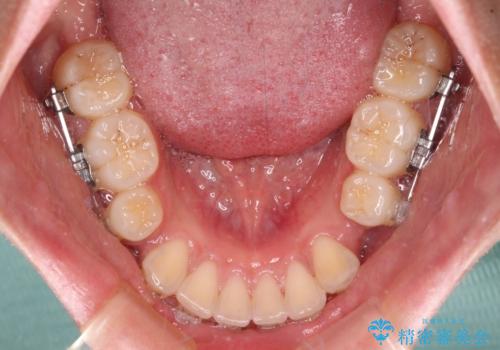

- クリアブラケット

口元の突出感を改善するため、上下左右第一小臼歯4本の抜歯を行い、ワイヤー装置による矯正治療を行うこととしました。

舌の突出癖により上下前歯は非接触であり、非常に前方に飛び出している状態でした。

舌のトレーニングをしっかりと行っていただき、口の閉じやすい歯並びに仕上げることができました。